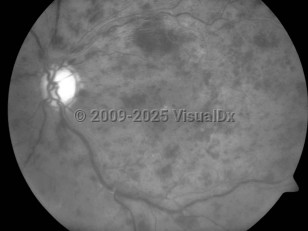

Central retinal vein occlusion - External and Internal Eye

The occluded central vein can lead to intraretinal hemorrhage, exudation of fluid, varying levels of ischemia, and neovascular complications such as neovascular glaucoma. CRVO is commonly classified by severity into 2 forms: the nonischemic form of CRVO, which is milder and more common, and the ischemic form, which results in more severe retinal damage and vision loss. In ischemic CRVO, more than 90% of patients have vision of 20/400 or worse. One-third of patients with the nonischemic type progress to the ischemic type.

Iris neovascularization, which is associated with neovascular glaucoma, occurs in up to 60% of patients with the ischemic form, usually 3-5 months following the obstruction. The main risk factors for development of neovascular glaucoma after a CRVO are the extent of capillary nonperfusion, poor visual acuity, severe venous tortuosity, and retinal hemorrhage.